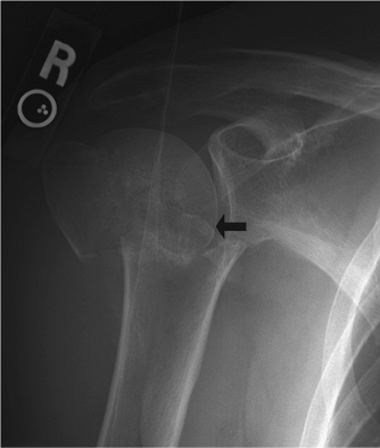

fixation. When a valgus-impacted fracture is identified, one must

carefully look for evidence of lateral displacement of the humeral-head

fragment (Fig. 3.4). If lateral displacement is

found, the medial periosteal vessels that perfuse the articular segment

may be ruptured, and avascular necrosis is more likely to result. In

the absence of lateral displacement of the humeral-head fragment, the

humeral head is likely to remain viable.

Figure 3.4.

A valgus-impacted fracture with more than 5 mm of lateral displacement of the humeral head. This may signify disruption of all soft-tissue attachments to the articular segment. |